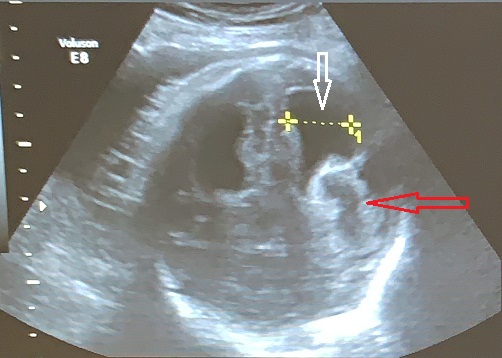

Columna vertebral

La columna vertebral, el eje neurológico que articula las funciones motrices y autonómicas del cuerpo comandadas por el cerebro y los sistemas vegetativos, es una estructura lineal mas sencilla de evaluar pero no menos importante desde el punto de vista diagnóstico por ser el asiento de las malformaciones más comunes del sistema, la espina bífida.

Las estructuras intracraneales después de la semana 18-20 del embarazo son muy características y permanecen visualmente invariables hasta el final del embarazo, solo modificando sus tamaños a medida que el feto crece. Esto es de gran ayuda ya que permite determinar la aparición de cambios que podrían sugerir desviación de la normalidad y aparición de una malformación congénita o lesión adquirida por eventos externos especialmente relacionados a infecciones y accidentes vasculares fetales.